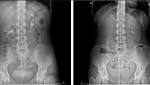

- This Woman's Kidney Fell into Her Pelvis Whenever She Stood Up: Here's Why Live Science

- What is a Floating Kidney? Woman's Organ Drops into Pelvis Every Time She Stands Up Newsweek